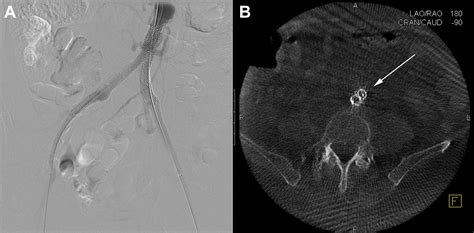

Catheter Angiography Invasive gold standard Used primarily during intervention to visualize flow while treating the blockage.

• Endovascular Therapy: This includes balloon angioplasty and stenting. It is minimally invasive, typically involving a small puncture in the groin to access the vessel, and allows for a quicker recovery time.

• Hybrid Procedures: A combination of endovascular techniques and traditional surgery tailored to the patient’s specific vascular anatomy.